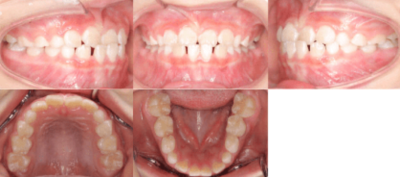

<治療前>

<治療後>

初診時は7歳2ヶ月で、前歯のかみ合わせが反対になっていることが主訴で来院されました。前歯部の反対咬合の診断により、「マウスピース型カスタムメイド矯正歯科装置(製品名インビザライン・ファースト 完成物薬機法対象外)」を使用して治療を開始しました。

治療期間は6ヶ月で、下顎の前歯が上顎の前歯より前に出ている「交叉咬合」が改善されました。

治療のリスクとしては、矯正治療時に歯が移動する際に生じる痛み、歯根の吸収、むし歯が挙げられます。治療費用はおよそ40万円です。